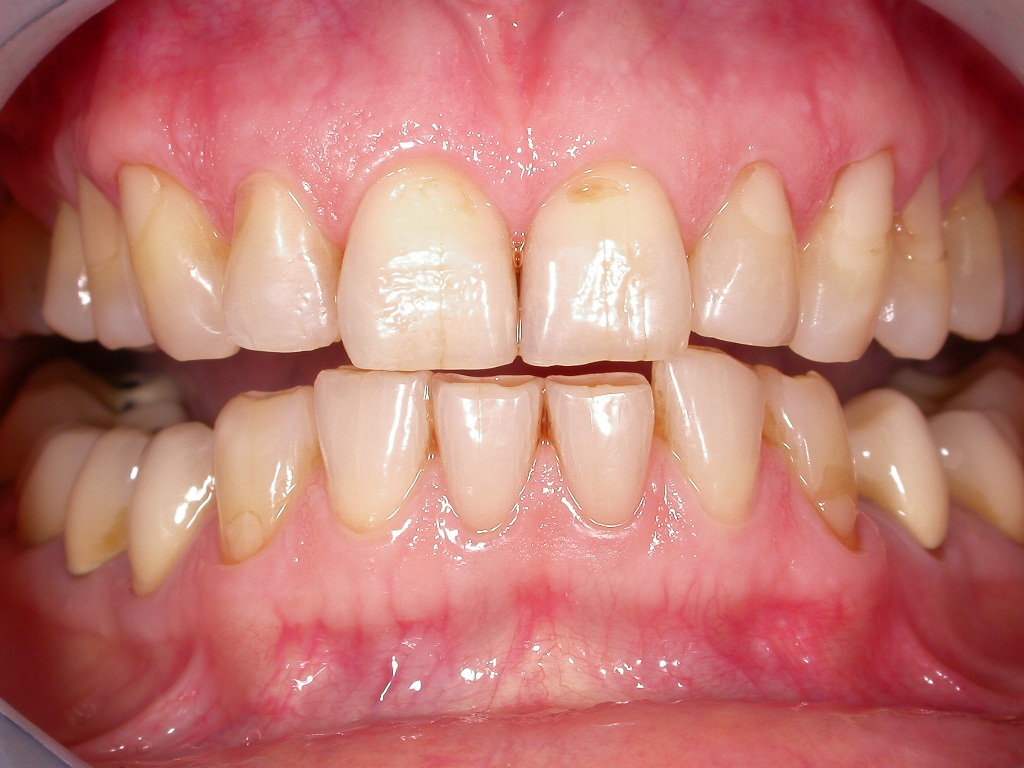

Verfärbte Zähne und freiliegende Zahnhälse

Vorher: Verfärbte Zähne und freiliegende Zahnhälse

Ästhetische Optimierung mit vollkeramischen Veneers und Kronen in nur 2 Terminen

Nachher: Ästhetische Optimierung mit vollkeramischen Veneers und Kronen in nur 2 Terminen